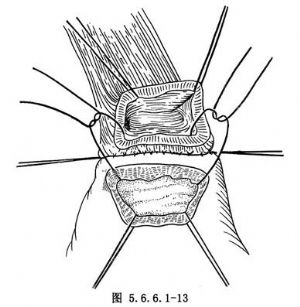

(4)常规食管胃端侧吻合:①先在预计切断食管的平面上方1cm处由食管边缘两侧分别用丝线穿过肌层与黏膜下层,与胃底部预计切开处的浆肌层缝合,两针之间的距离为食管的宽度(图5.6.6.1-10),图中食管壁上的虚线为准备切断食管的平面;②在两根缝线之间加缝数针,将食管后壁与胃底部浆肌层完全缝合(图5.6.6.1-11),图中胃壁上虚线为准备切开胃壁的部位;③切开胃壁浆肌层,但勿切透黏膜,将循行于黏膜下的每根血管用细丝线缝扎两处,然后在缝扎线之间切开胃黏膜。黏膜上切口开始不宜太大,在吻合过程中如嫌不足可再次切开(图5.6.6.1-12)。在切开胃壁之前应先用干纱垫置于吻合口后方以吸取切开胃黏膜后逸出的胃液,切开胃黏膜后迅速将吸引器头送入胃中吸净胃液;④沿预计切断食管的平面环绕食管切开肌层但勿切开黏膜,在食管肌层断面远侧约0.8cm的平面剪断食管黏膜,因留有足够的黏膜,吻合时十分便利,否则如在同一平面切断食管肌层及黏膜,由于后者的回缩使吻合操作相当困难;⑤将吻合口后壁食管全层的左右侧两角分别与胃壁切口的上缘全层用细丝线间断缝合,注意食管黏膜与胃黏膜必须对齐,缝线之间的间隔约为0.4cm,缝线结扎不能太紧以免术后局部组织水肿造成切割,成为发生吻合口瘘的主要因素(图5.6.6.1-13)。结扎线结打在腔内(图5.6.6.1-14);⑥将胃管经吻合口送入胃中,如果应用十二指肠饲食管,可在此时将引导饲食管的糖球一并送入胃中(图5.6.6.1-15),开始吻合前壁。由后壁转往前壁时,两侧转角处的缝线必须缝好,因在转角处容易发生瘘。吻合的最后4~5针最好先挂上线而不结扎,待全部缝合完毕时一次打结;⑦前壁第一层吻合完成以后,撤除原来置于吻合口后方的干纱布块,参加手术人员用无菌净水冲洗手套,将吻合使用过的器械前端用水洗净,用细丝线间断缝合吻合口前壁第二层,完成食管肌层及黏膜下层与胃底部浆肌层之间的缝合(图5.6.6.1-16);⑧将吻合口周围的胃壁用纱布向吻合口方向推送,结扎吻合口前壁第二层的缝线,使吻合口最后被套入胃壁中(图5.6.6.1-17);⑨将胃内引导十二指肠饲食管的糖球挤过幽门,清点台上敷料(包括纱布及纱垫)无误后,用中号丝线间断缝合膈肌。在胃越过膈肌处缝合不宜过紧,防止术后出现梗阻。将胃轻轻上推然后将胃壁与周围膈肌缝合6~7针,防止腹腔内脏器循此途径进入胸腔。注意不要用丝线将胃壁固定在胸壁上,此种缝线可能造成胃壁穿孔。如术者想采取措施减少吻合口的张力,可在近胃底部的胃大弯侧寻找一个切断大网膜的残结,用缝线穿过固定在纵隔胸膜上,同样可以达到吻合口减张的目的而无胃壁穿孔之虞。由第8肋间腋后线置入闭式引流管,检查胸内有无出血点或异物存留。用肋骨合并器将切口上下方的肋骨合拢,肋间组织用中号丝线缝合,冲洗胸壁肌肉,逐层关胸。将闭式引流管连接于水封瓶上。